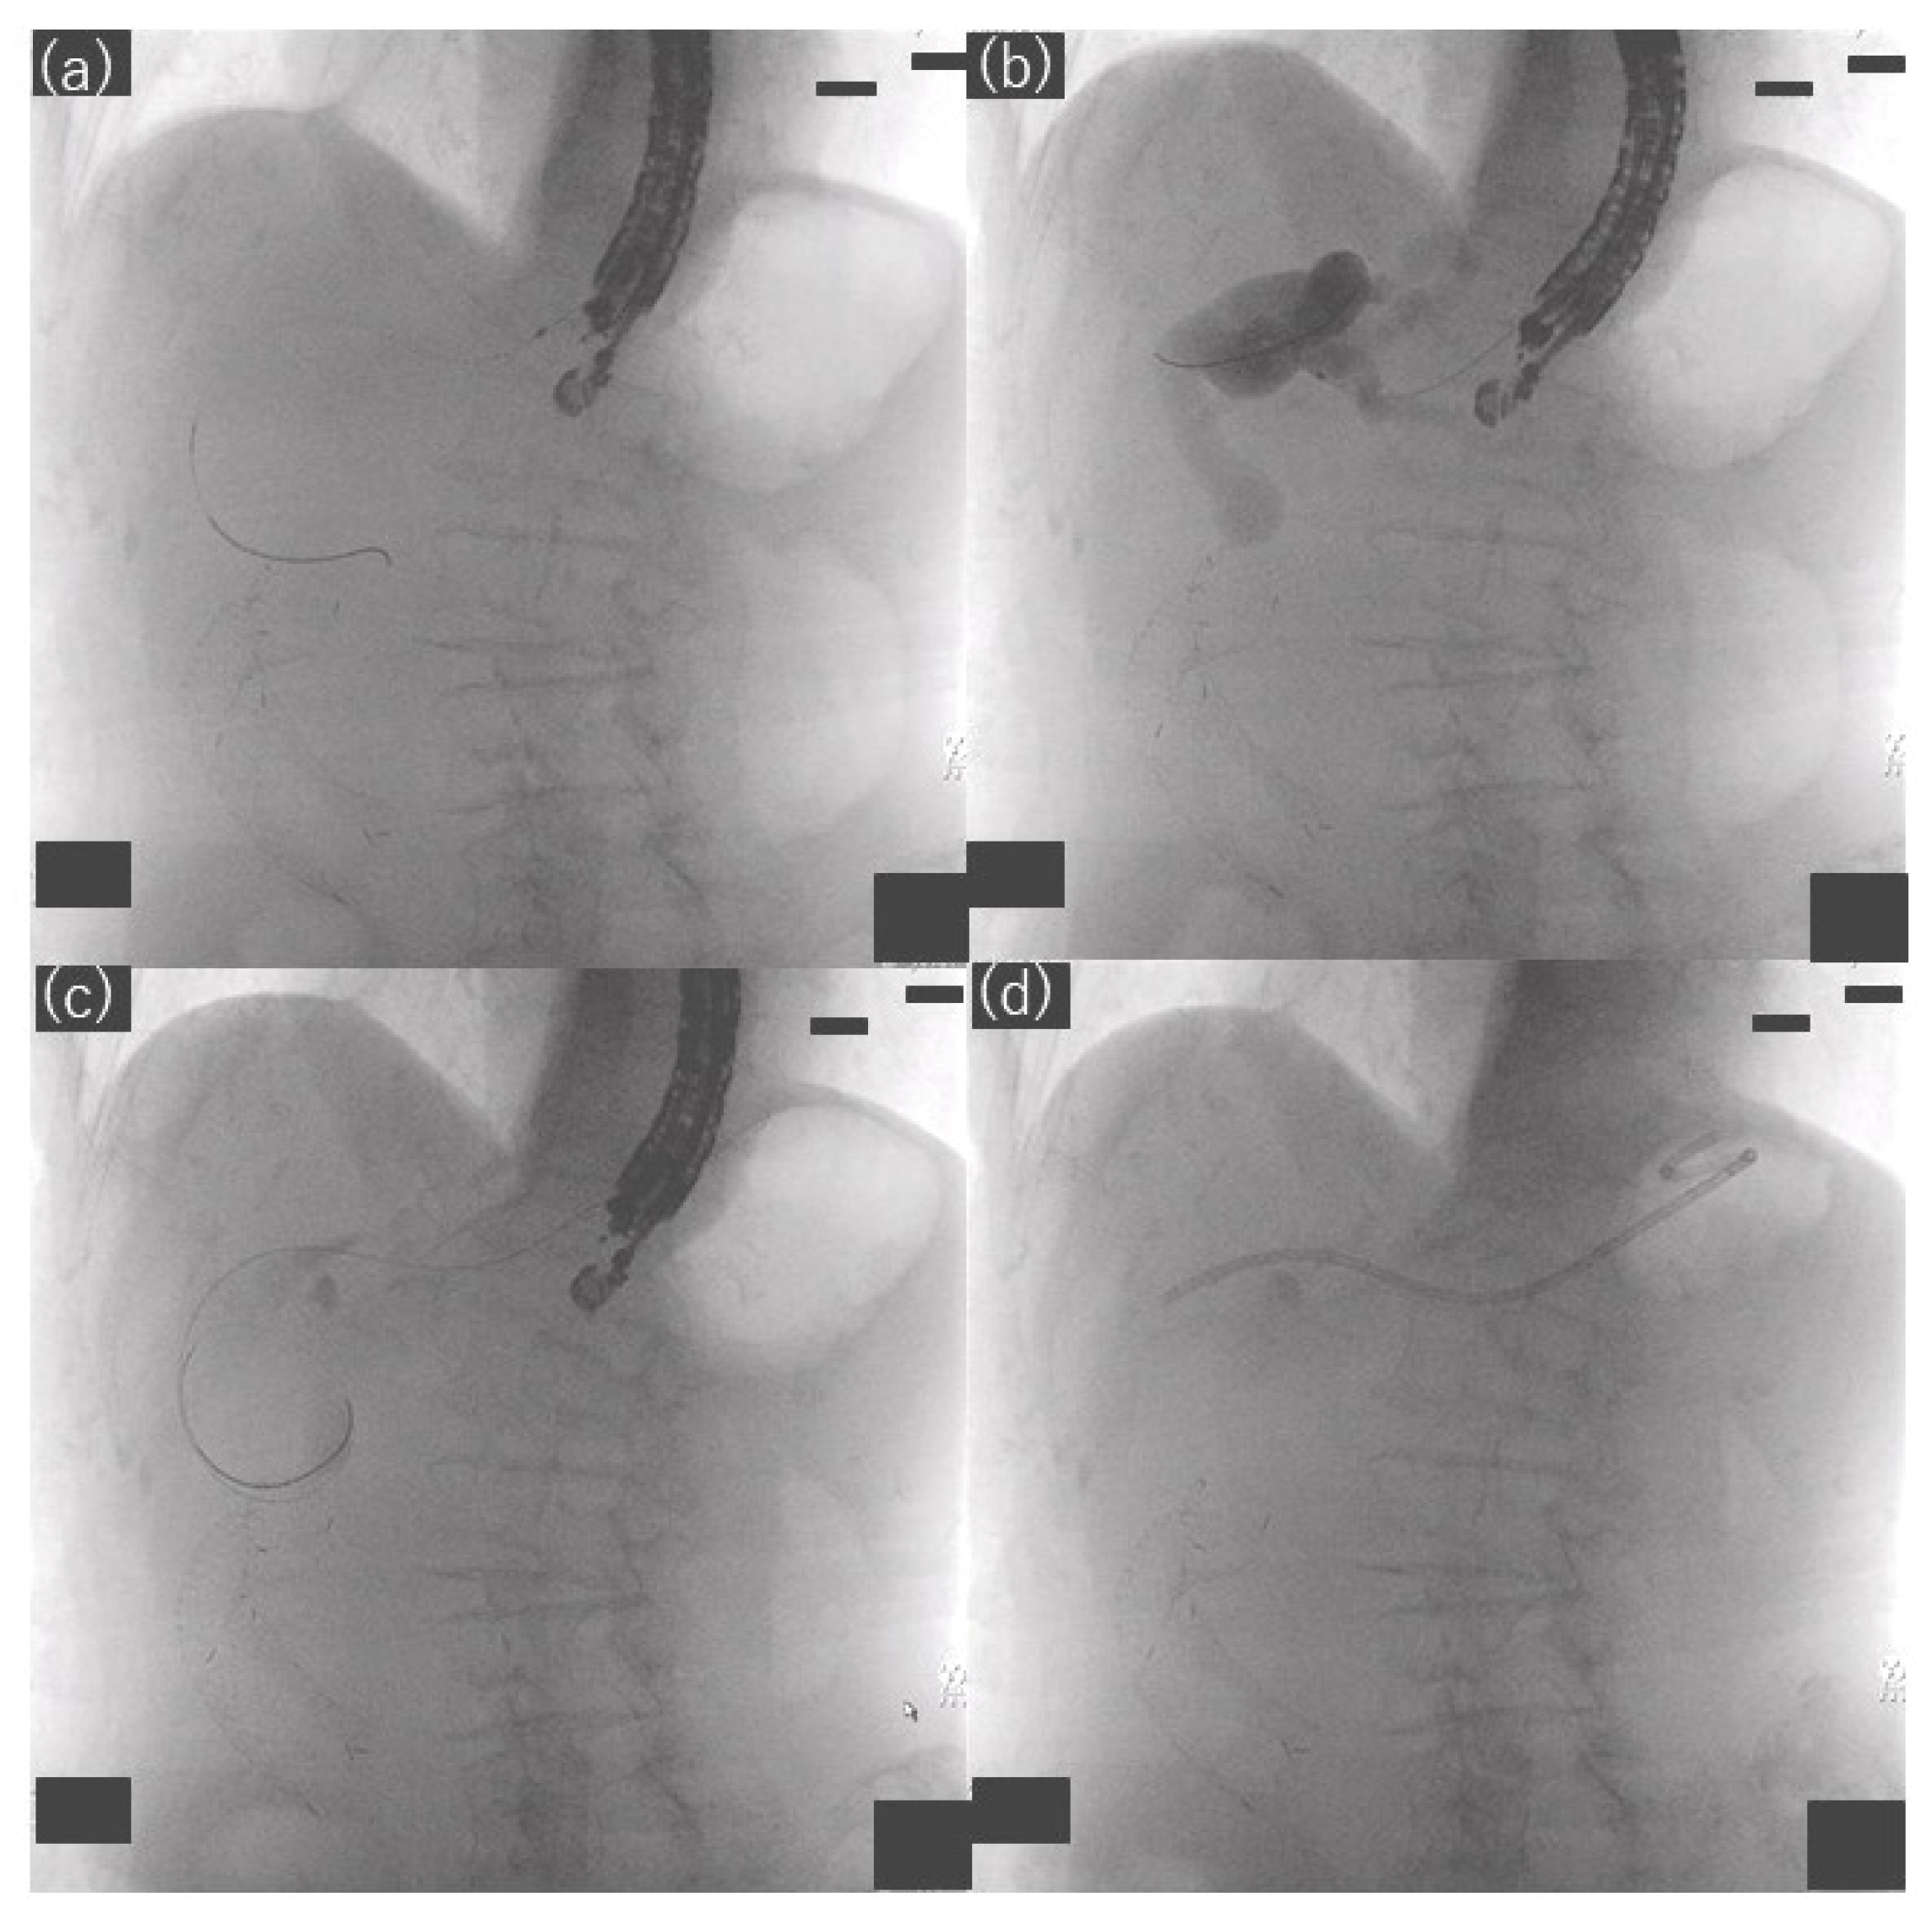

2.3. Procedures